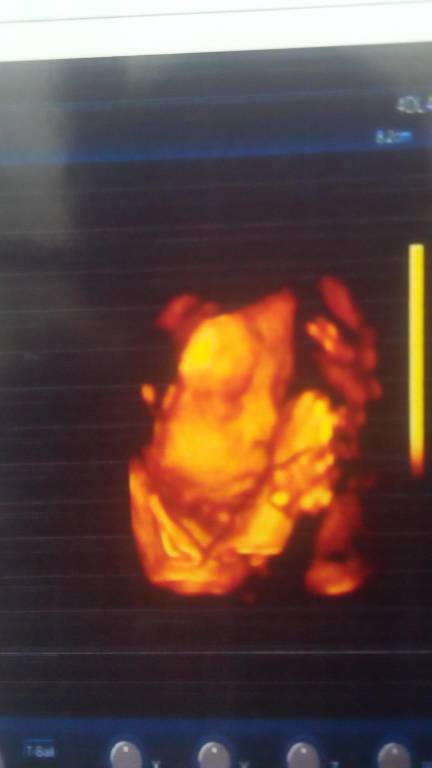

四维归来男宝一枚 宝贝儿子妈妈爱你 四维归来男宝一枚 宝贝儿子妈妈爱你 点击展开 。有①种情、叫不弃” 2014-12-25 16:07 为您推荐: 其他回答 恭喜宝妈。 159*****361_dml8 2014-12-25 21:21 祝宝妈好孕 洛洛阿 2014-12-25 17:08 恭喜。。。 依依*嘟嘟 2014-12-25 16:56 现在不是不告诉男女吗? &小女人&_4X41 2014-12-25 16:54 恭喜宝妈。 An娜 2014-12-25 16:52 加载更多 相关问题 四维顺利归来 宝贝 妈妈爱你 四维健康通过,开心 宝贝你就是妈妈的动力 爱你宝贝 我还有一个星期就可以去做四维彩超了!真的好期待…希望宝贝一定要好好的 妈妈爱你